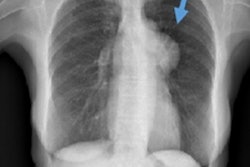

Detection errors were most often a question of perception and can be minimalized by comparison with previous studies, structural analysis of critical areas -- in the chest these being the upper lobes, the perihilar region, and the back, according to Schaefer-Prokop. Grayscale reversal and digital processing tools also help optimize data.

In terms of interpretation errors, causes were often insufficient knowledge of clinical history, absence of previous studies, the presence of a more obvious abnormality, and a lack of experience in the reader. "Not everything that looks like a tumor is a tumor," she said. "You don't want to get sued by the man who thinks he's dying of bronchogenic carcinoma and spends all his money, only to find that the lesion disappears because you missed the infectious disease that caused it."